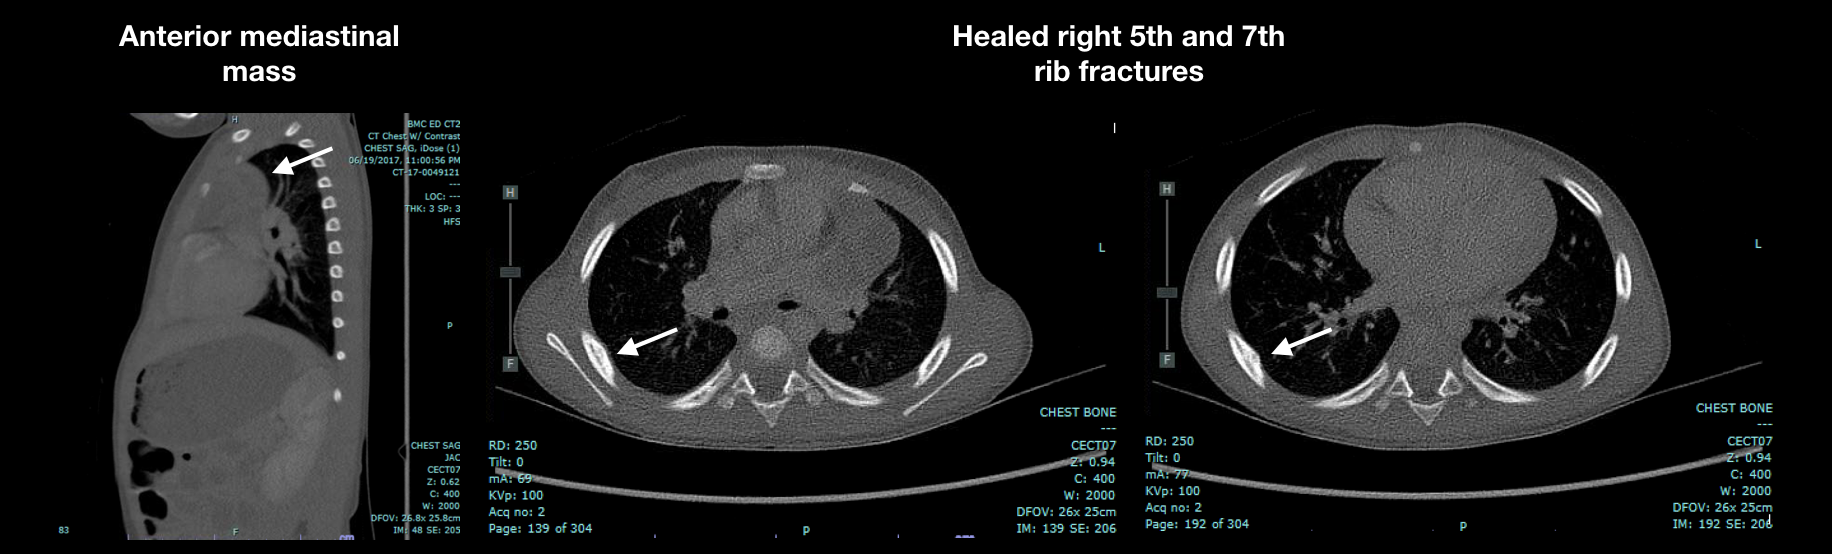

Prior to this ED visit, she awoke with bruising over her right ear and anterior chest. Her vital signs show her to be afebrile, normotensive, tachycardic to 124 bpm, and tachypneic to 30 breaths/min. Physical exam reveals her to be alert and appropriate, with visible bitemporal circular bruises; bruises on right ear pinna and posterior auricular area; and 3 circular anterior chest bruises at clavicular level. Lab findings include WBC 9.3 K/mm3, Hgb 9.3 g/dL (MCV 68.9 fL) PT 11.9s (INR 1.1), PTT 24.1s, ESR 22 mm/hr, platelet 423 K/mm3, lipase U/L, uric acid 6.5 mg/dL, phos 5.3 mg/dL, creatinine 0.3 mg/dL, AST 965 U/L, ALT 1302 U/L, uric acid 6.5 mg/dL, LDH U/L 994, alkaline phosphate 859 IU/L. Chest x-ray shows new smooth bony contour convexities at the inferolateral aspect of the right 5th and 7th ribs. Repeat chest CT scan reveals no changes in the mass, but healed right 5th and 7th rib fractures are identified on posterior thorax. Non-accidental trauma (NAT) is diagnosed and custody of child is obtained by the DCF. Ultimately she is referred to a quaternary care children’s hospital where biopsy reveals multiloculated thymic epithelial cyst, uninvolved thymus gland, and no evidence of malignancy. The etiology of the spontaneous TLS remains unclear.